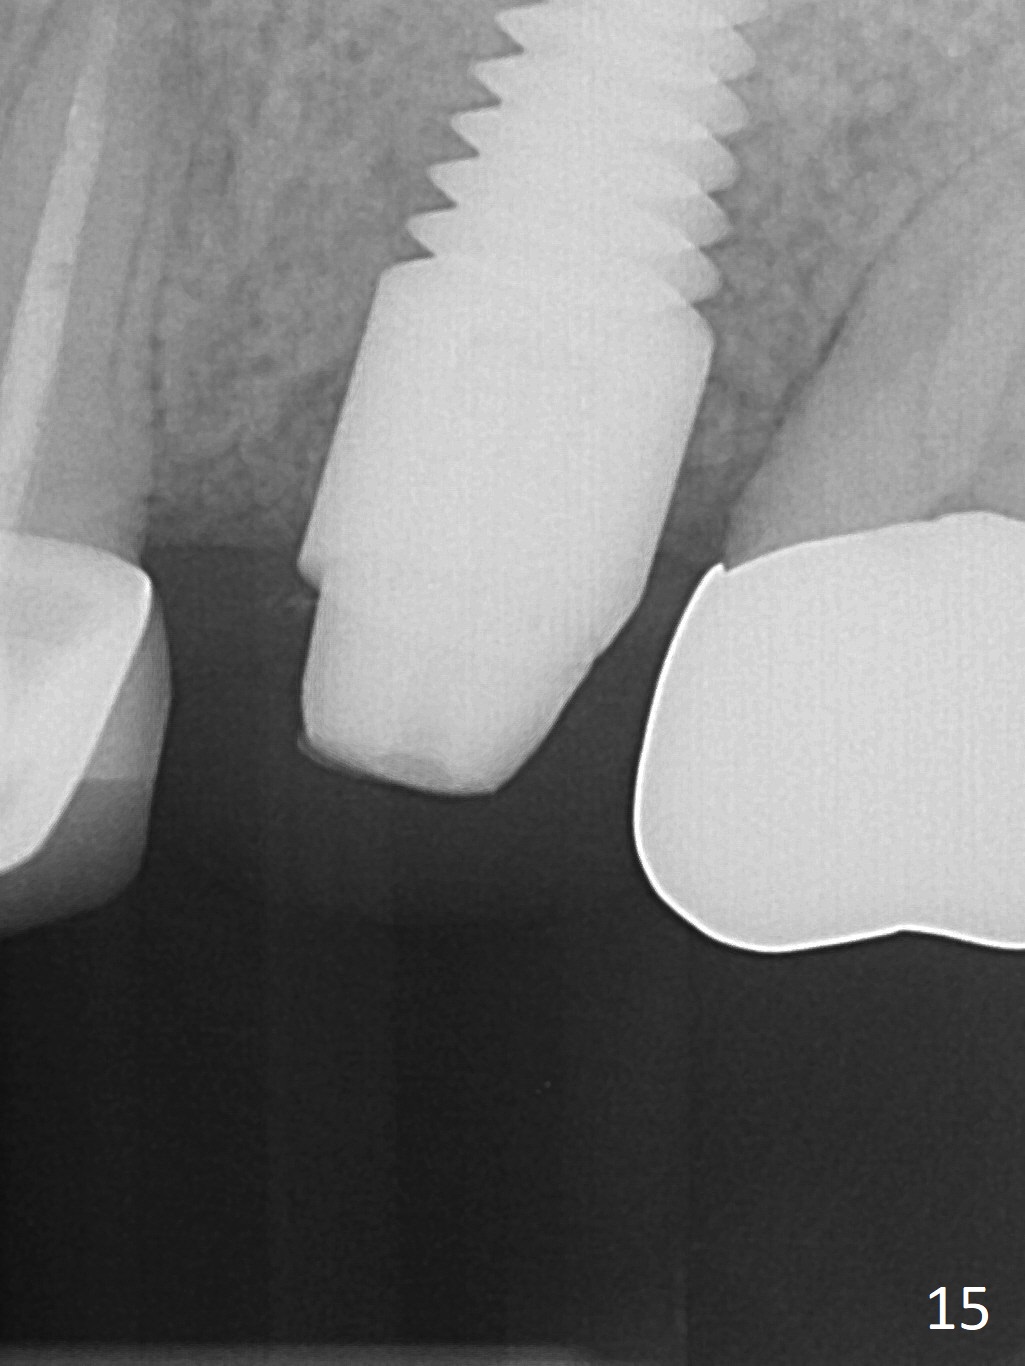

The patient is doing well 9 days postop.  The immediate provisional is loose and over-sized.  It is removed for trimming and reline; the socket and bone graft (Fig.8 *) are healing.  It appears that an angled abutment is required next time of provisional revision.  When an angled abutment is being placed 23 days postop (Fig.9), it appears to wiggle the implant due to its long leverage.  Instead a healing abutment is placed.  The implant is unstable 4.5 months postop with seemingly excessive bone-implant gap (Fig.10 <).  The 5.5x9 mm implant is removed.  A 5x17 mm tap is used to change the trajectory and sinus lift, followed by 6x17 one (Fig.11).  Finally a 6x14 mm tissue-level implant is placed with insertion torque > 50 Ncm (Fig.12; vs. <20 Ncm (Fig.7,10)) and improved trajectory.  An immediate provisional is fabricated to prevent the mesial drifting of the tooth #15 (Fig.13 P (*: occlusal clearance)).  By using the taps and placing the longer implant, the sinus lift is more obvious (compare Fig.10 and 12 (*)).  Sinus lift remains evident 3.5 months postop (Fig.14) with apparently osteointegration (Fig.15).